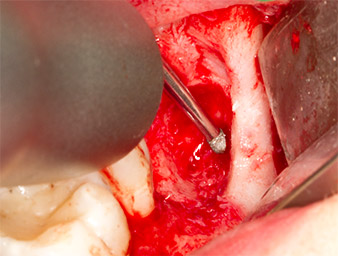

À l'aide d’un insert pour le débridement parodontal (Piezomed P1), l’espace ligamentaire parodontal de la racine résiduelle est ensuite élargi de manière minimale (Fig. 8).

Le même insert activé est inséré dans le canal radiculaire et détache le fragment sous l’effet de ses vibrations à micro-oscillations (Fig. 9, 10).

Piezomed P1

Fig. 9 : L’insert Piezomed P1 est recommandé par le fabricant essentiellement pour le débridement parodontal mais il est également adapté à la chirurgie. Ici, il est placé dans le canal radiculaire après élargissement minimal de l’espace ligamentaire parodontal.

Fig. 10 : Grâce à sa forme très affinée, l'insert peut pénétrer dans le canal radiculaire et extraire le reste radiculaire sous l’effet des micro-oscillations (vibrations).